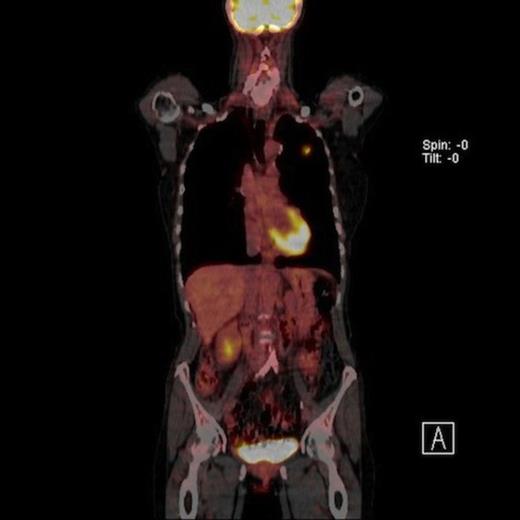

A 61-year-old female smoker (42 pack years) was found to have left upper zone shadowing on chest X ray following a history of weight loss. Her performance status was 1 with a Forced expiratory volume in one second (FEV1) of 1.94 Litres. Positron emission tomography in conjunction with computed tomography (PET-CT) showed two nodules in the left upper lobe. There was a 2cm spiculated lesion in the anterior segment with a Standardised Uptake Value (SUV) max of 5.6 units (Fig 1A) and a 2.2 cm cavitating lesion in the apico-posterior segment with a SUV max of 2.7 units (Fig 1B). There was no radiologic evidence of mediastinal lymhadenopathy or distant metastases.

Coronal view of PET CT scan of moderate uptake synchronous nodule in the left upper lobe